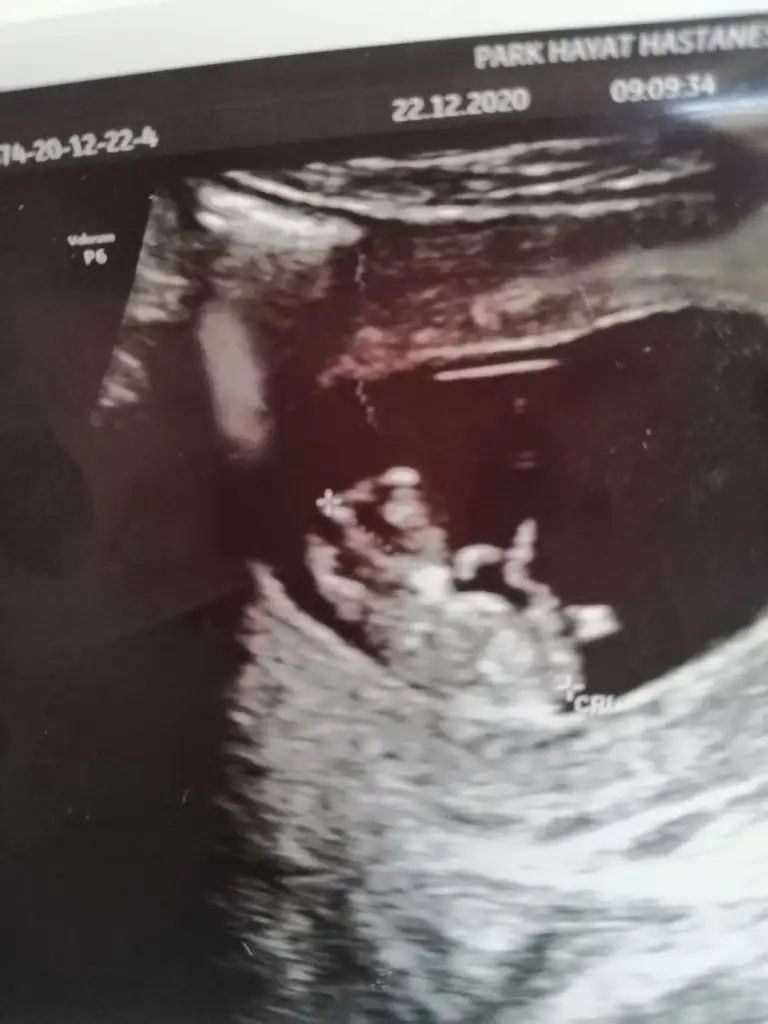

Doğru tahmin etmişsiniz doktorum da bugün kız dediKız gibi

Aslında okla gösterdiğiniz yeri ben ayak olarak düşündüm deKız gibi geldi nubu banaumarım gonlunuzdeki olsun inşallahEki Görüntüle 2748350

Saglikla gelsin insAma kafası ayni erkek :)

Aşk olsunErkek bence bebegın